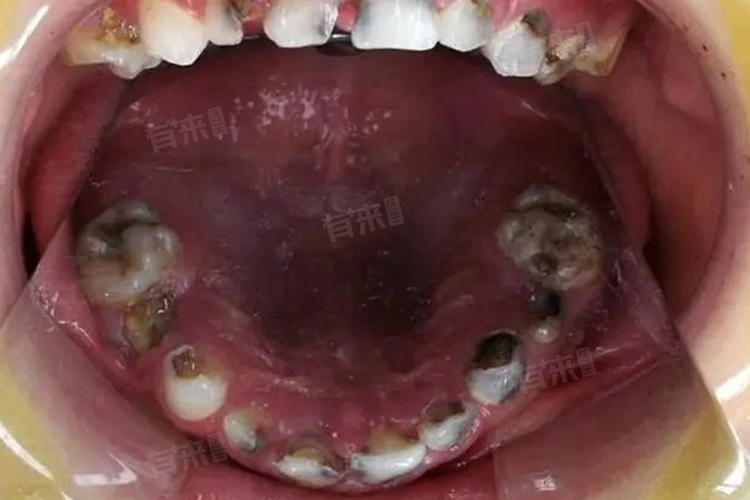

3、龋齿:龋齿是牙齿硬组织逐渐破坏的一种疾病,初期可能仅表现为牙齿表面的小黑点或白垩色斑块,但随着病情发展,龋坏组织会逐渐扩大并深入牙髓,导致牙齿发黑甚至疼痛,龋齿的形成与口腔卫生、饮食习惯等密切相关。一旦发现龋齿,应及时就医治疗,以免病情恶化。

4、牙髓坏死:牙髓是牙齿内部的软组织,负责牙齿的营养供应,当牙髓因外伤、感染等原因坏死时,牙齿会失去营养来源,逐渐变得灰暗甚至发黑,通常伴有剧烈疼痛,严重影响生活质量。对于牙髓坏死的牙齿,需进行根管治疗以清除病变组织,并考虑进行冠修复以恢复牙齿功能和美观。